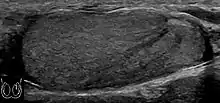

![]() Sonography of a normal testis. The normal testis presents as a structure having homogeneous, medium level, granular echotexture. The mediastinum testis appears as the

hyperechoic region located at the periphery of the testis as seen in this figure. | |

The normal adult testis is an ovoid structure measuring 3 cm in anterior-posterior dimension, 2–4 cm in width, and 3–5 cm in length. The weight of each testis normally ranges from 12.5 to 19 g. Both the sizes and weights of the testes normally decrease with age. At ultrasound, the normal testis has a homogeneous, medium-level, granular echotexture. The testicle is surrounded by a dense white fibrous capsule, the tunica albuginea, which is often not visualized in the absence of intrascrotal fluid. However, the tunica is often seen as an echogenic structure where it invaginates into the testis to form the mediastinum testis. In the testis, the seminiferous tubules converge to form the rete testes, which is located in the mediastinum testis. The rete testis connects to the epididymal head via the efferent ductules. The epididymis is located posterolateral to the testis and measures 6–7 cm in length. At sonography, the epididymis is normally iso- or slightly hyperechoic to the normal testis and its echo texture may be coarser. The head is the largest and most easily identified portion of the epididymis. It is located superolateral to the upper pole of the testicle and is often seen on paramedian views of the testis. The normal epididymal body and tail are smaller and more variable in position.